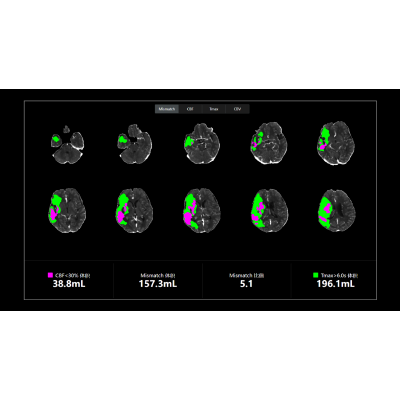

联影智能CTP脑灌注智能分析系统可自动重建灌注参数图(CBV、CBF、MTT、TTP、Tmax)与tMIP图像,精准定位与定量分析低灌注区、核心梗死区及错配(Mismatch)区域,可对CBV、CBF、Tmax进行多阈值分析,支持15个脑区自动分割并提供异常脑区分析,自动生成智能报告,支持智能胶片打印与归档,辅助医生多方位评估患者脑血流灌注情况,精高效诊疗。

联影智能CTP脑灌注分析系统能够定量地分析出核心梗死区、低灌注区与错配区,还能够提供CBF、CBV、Tmax等多参数、多阈值分析,以充足的量化信息为辅助医生全方位精准评估脑血流灌注情况,为患者提供更好的治疗决策。